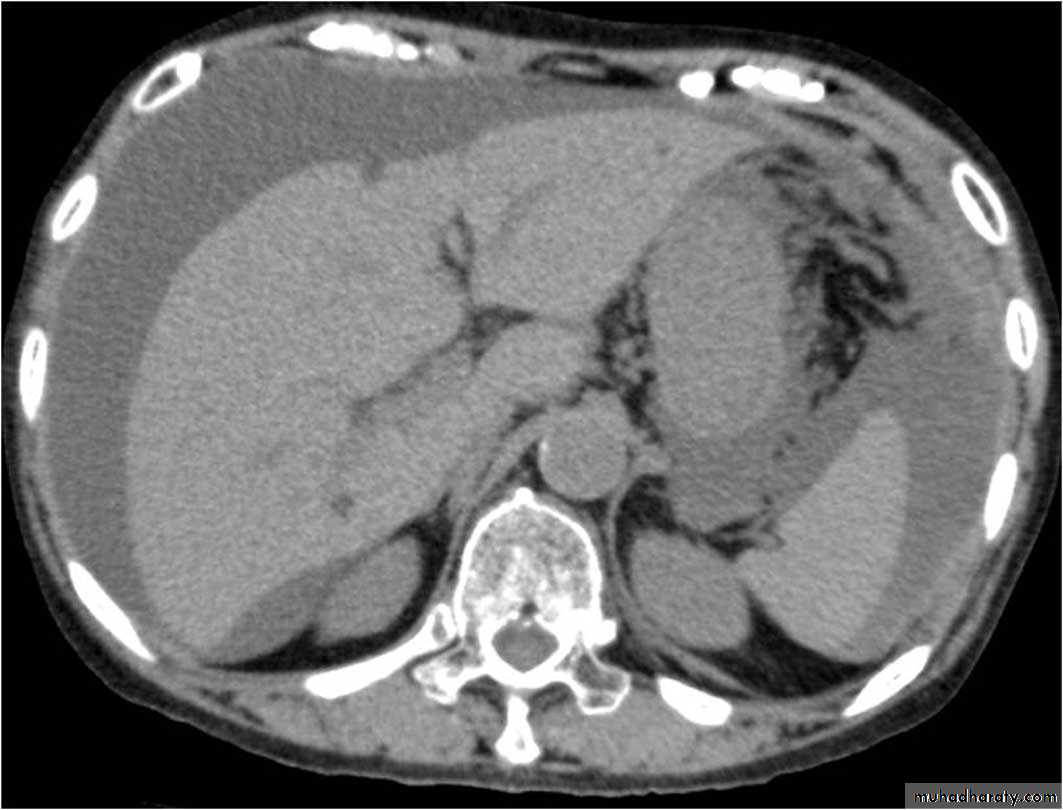

Retroperitoneal tumor